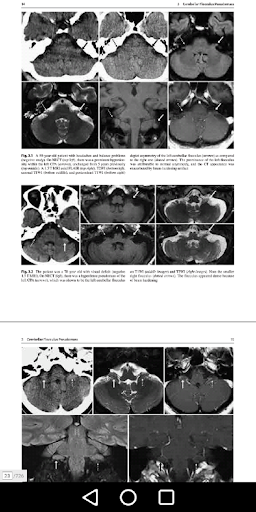

Vasculature CraniOcervical: Pengenalan

Aortic Arch dan Vessel Vessel Asal Arterial Varions

Variasi Arteri Cervical dan Vertebral Arteri

Arteri Serviks dan Intracranial dan Basilar-Carotid Dolichoectasia